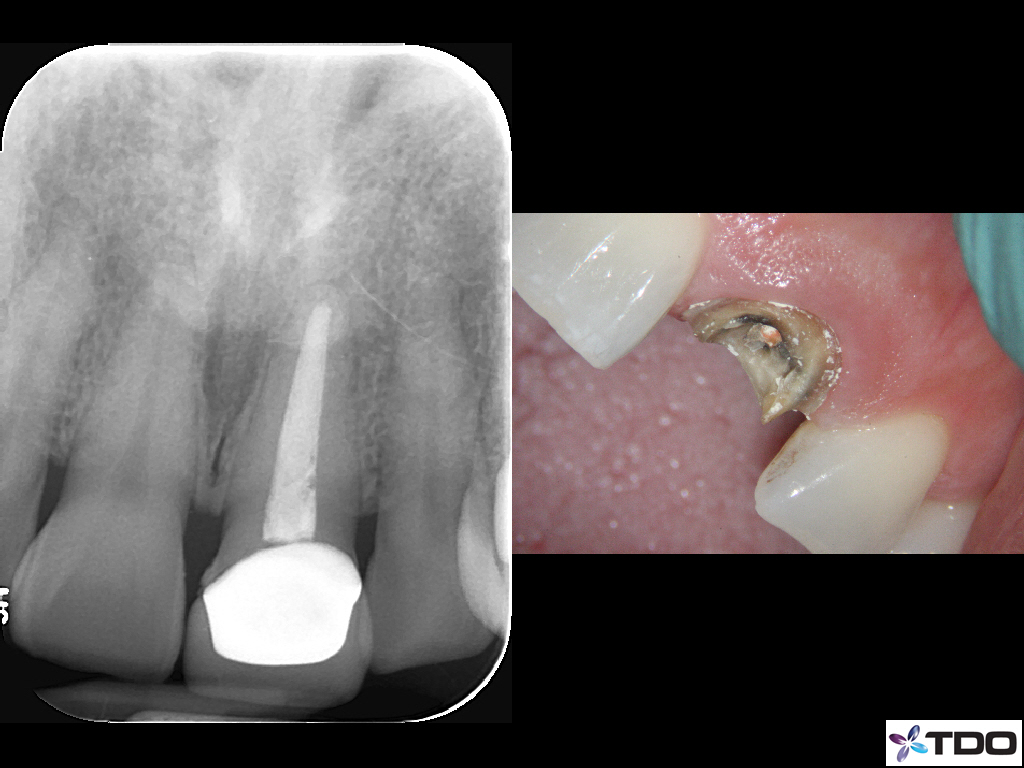

This patient fractured her front tooth.  The crown was only 2 years old.  Extraction and implant placement was recommended.  It would have been a challenging case esthetically.  We were able to retreat the contaminated root canal.  Posts were placed for reinforcement.  We were able to use the existing crown by retrofitting it.  We managed the occlusion to mitigate the risk of future fracture.